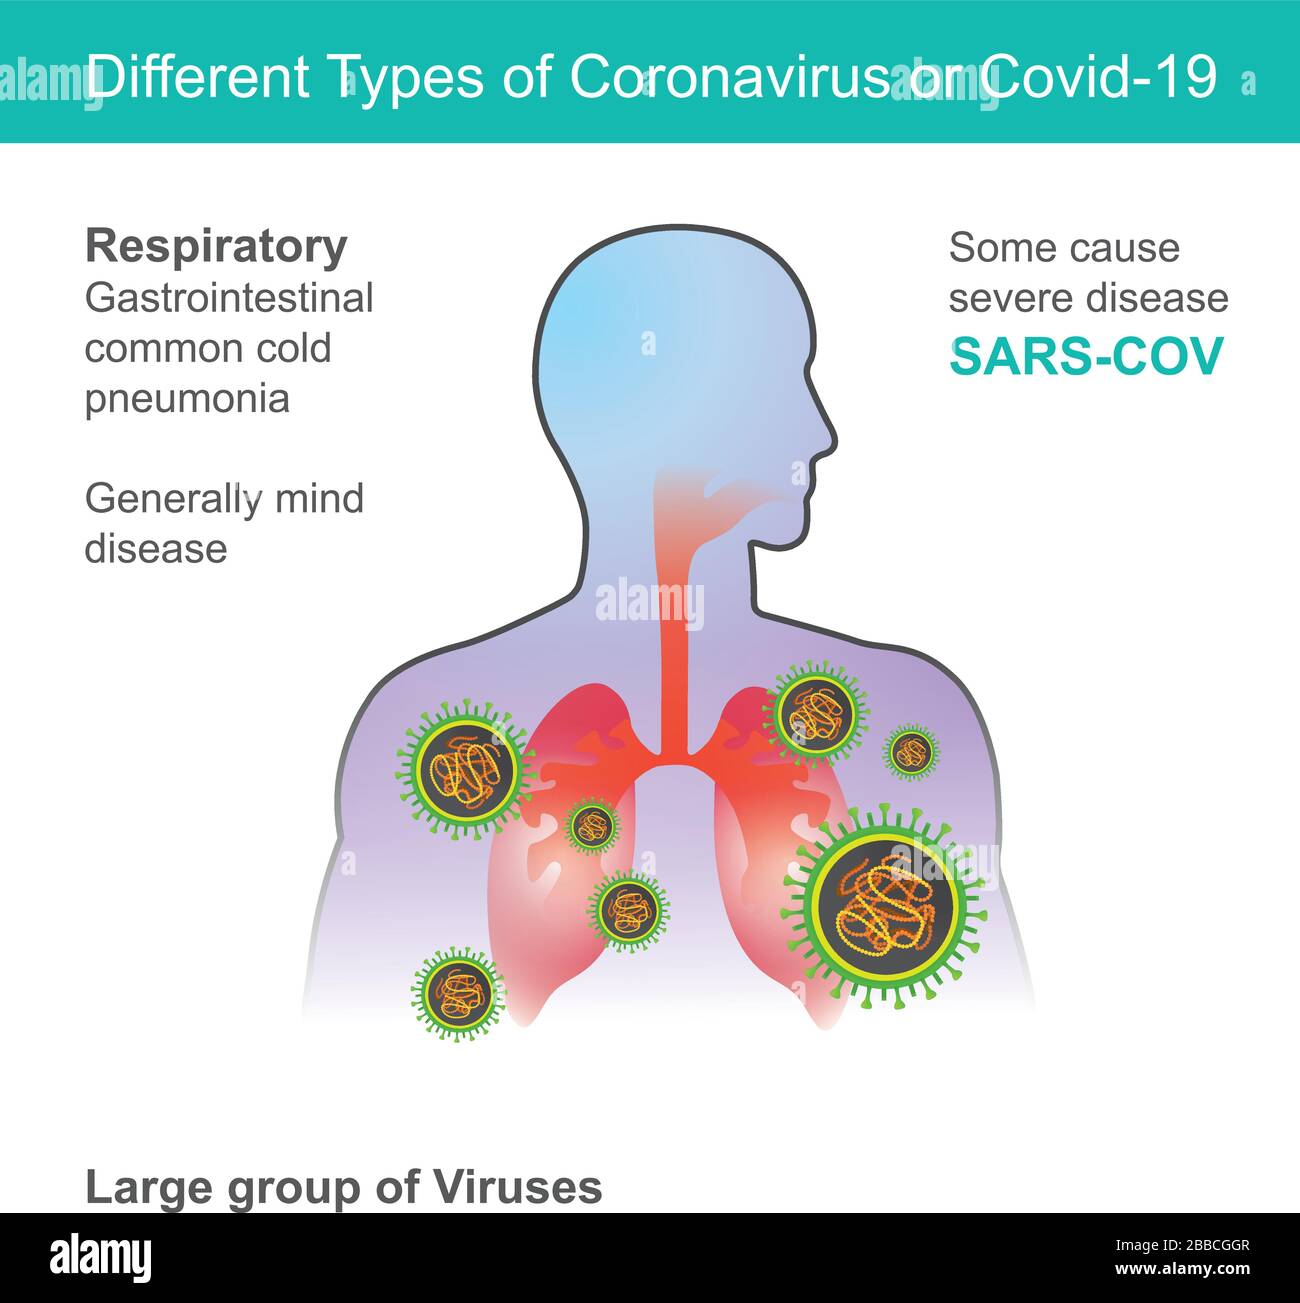

Diversi tipi di Coronavirus o Covid-19. Illustrazione sanità e medico. Illustrazione Vettorialehttps://www.alamy.it/image-license-details/?v=1https://www.alamy.it/diversi-tipi-di-coronavirus-o-covid-19-illustrazione-sanita-e-medico-image351245015.html

Diversi tipi di Coronavirus o Covid-19. Illustrazione sanità e medico. Illustrazione Vettorialehttps://www.alamy.it/image-license-details/?v=1https://www.alamy.it/diversi-tipi-di-coronavirus-o-covid-19-illustrazione-sanita-e-medico-image351245015.htmlRF2BBCGGR–Diversi tipi di Coronavirus o Covid-19. Illustrazione sanità e medico.